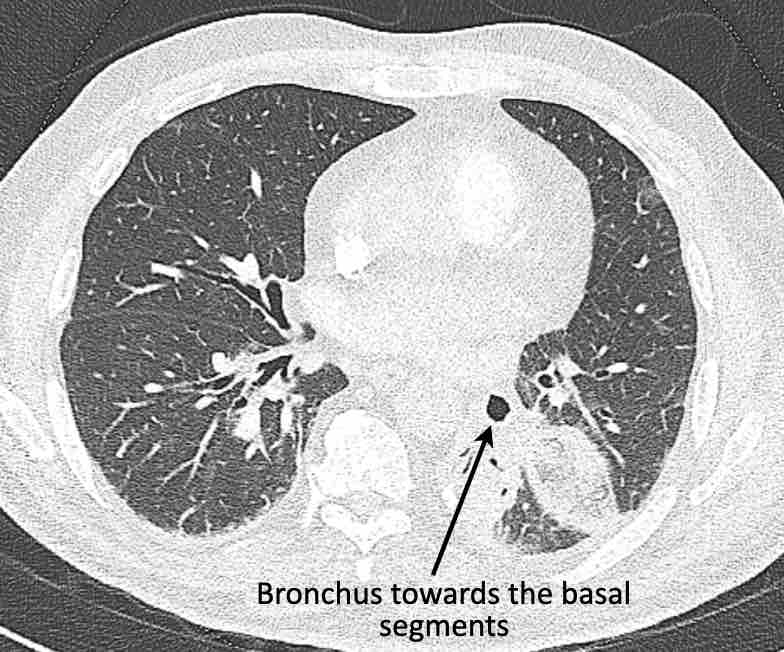

Cuộn qua các hình ảnh để quan sát khí quản phân chia thành phế quản chính phải và trái, sau đó tiếp tục phân chia thành các phế quản thùy và phế quản phân thùy.

Cuộn qua các hình ảnh để quan sát cách phổi được phân chia thành các phân thùy.